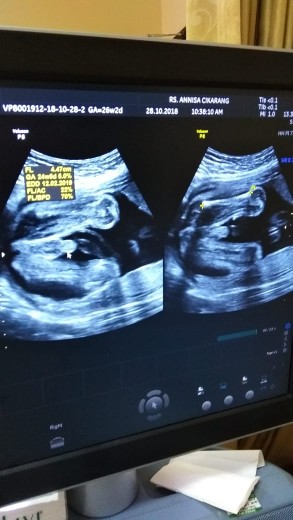

Ini pas ak 4d my baby cewe bun hehe

Udh berapa week moms ??.

Kmrn pas usg 31week bun